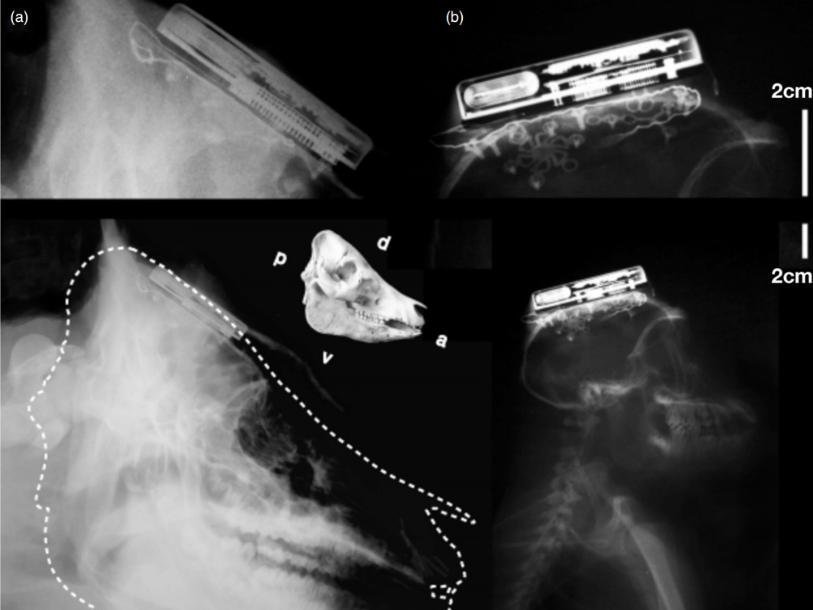

Имлантат размером 56мм х 42мм х 9мм заключен в титановый корпус. Он крепится под кожей на внешней стороне черепа, и лишь крошечный датчик толщиной около одного миллиметра вводится внутрь черепной коробки к моторной коре или другим областям мозга, в зависимости от преследуемых целей.

В отличие от шлемов, позволяющих передавать компьютеру мысленные команды без хирургического вмешательства, точность имплантатов во много раз выше, а возможность использования несравнимо шире.Как сообщается в статье, опубликованной в журнале Journal of Neural Engineering, в течение года новый чип проходил испытания на свиньях и обезьянах. При этом у животных не выявили никаких осложнений. Одной из немногих проблем, с которой исследователи столкнулись в начале работы, был нагрев корпуса во время зарядки. Им даже пришлось охлаждать «горячие головы» подопытных водой. Но впоследствии была использована индукционная беспроводная зарядка, позволившая избежать неприятностей. Последняя модель имплантата потребляет 100 милливатт энергии и может непрерывно работать в течение семи часов.